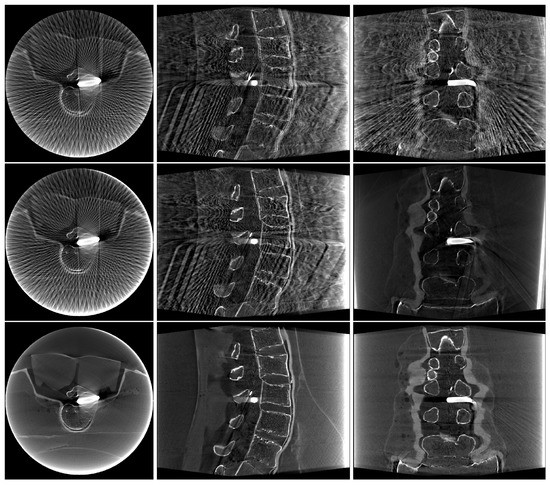

2.4. Image Data

3. Results